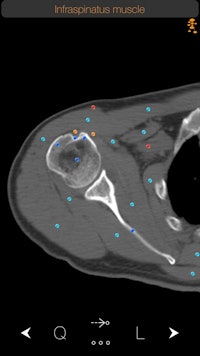

Normal infraspinatus muscle as shown on the CT Anatomy iOS app. Users can tap the dots for more information about each specific anatomical area. All images courtesy of iCat.The CT images used in the app come from nonpathological CT scans. At first we thought of using images from the [U.S. National Library of Medicine] Visible Human Project, and we acquired the relevant permission to do so. However, we soon realized that the Visible Human Project did not contain all parts of the human anatomy, and we wanted our images to have a consistency and continuity. So we decided to go with the option of using real patient scans. Obviously, we were very careful in obtaining copyright and ethical clearance from the patients and the hospital we worked with.

Users can access detailed descriptions of anatomy, as seen here in the description of the infraspinatus muscle.How many users do you currently have for the app?